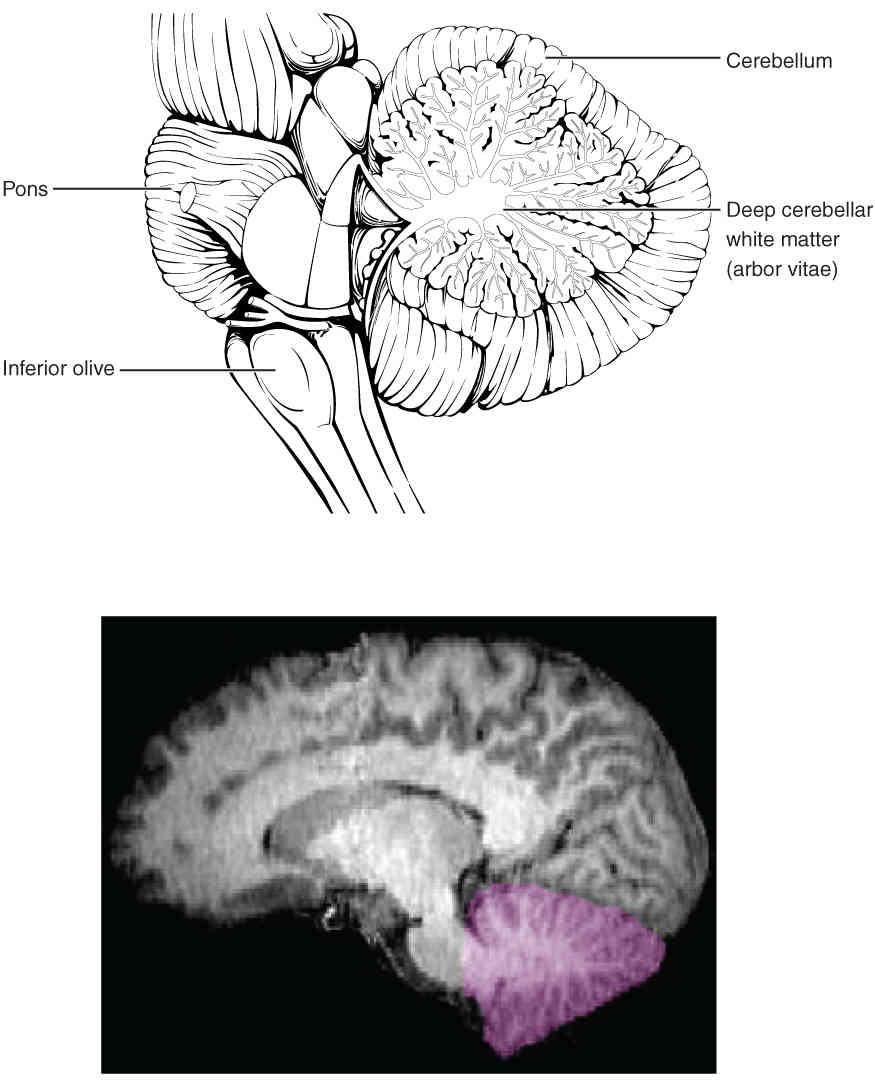

This page is under construction. For now, it is just a resource of the images found in the OpenStax Anatomy and Physiology Handbook. It wil slowly change into a revision tool. Each slide has a number. Use this to refer to the slide. When completed, it will have an unlabelled section, with labelled slides in parallel. On the unlabelled slides, write your answer and use the labelled slide to assess yourself. Keep track by also noting the number on each slide. Improvement at each attempt is important, more so than full marks on a first attempt.